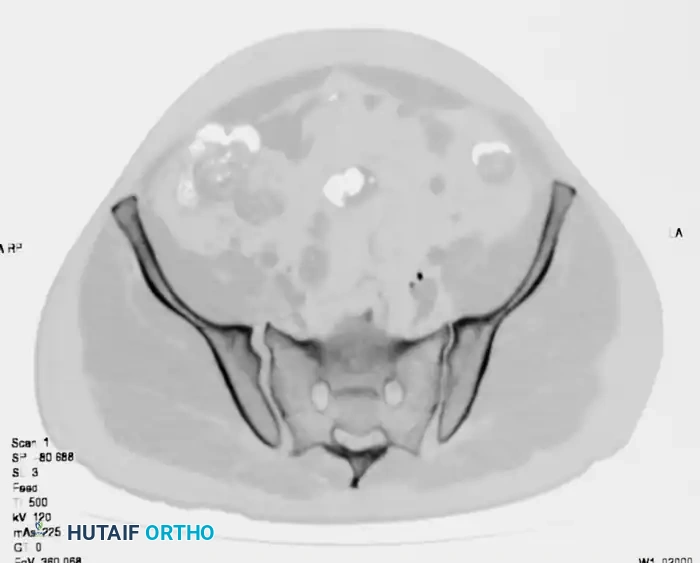

Axial CT imaging confirms the complete dissociation of the sacroiliac articulation, highlighting the profound instability of the posterior tension band.

FIGURE 56-45: Young and Burgess anteroposterior type III (AP III) pelvic ring injury with pubic diastasis and bilateral pubic rami fractures. A-C, Preoperative anteroposterior, inlet, and outlet views, respectively. D, Preoperative CT scan.